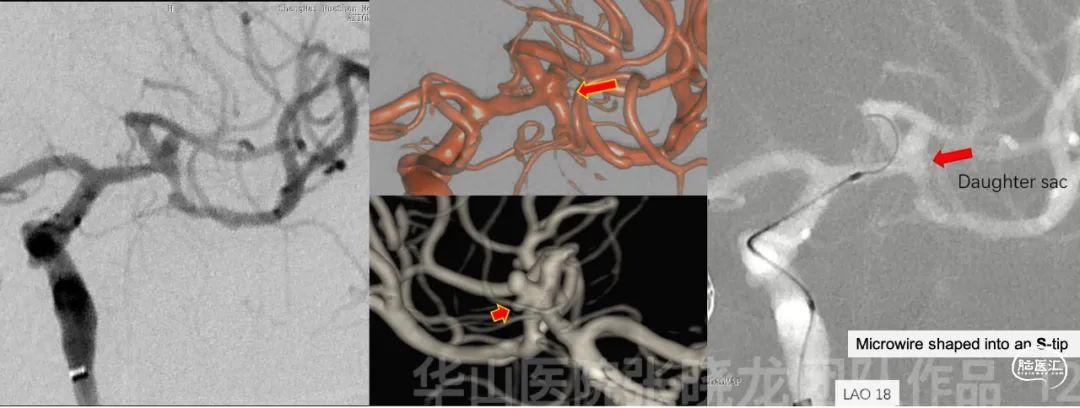

图 12. 测量。动脉瘤大小3.7*2.4mm,动脉瘤颈1.2mm。M1段直径2.2mm,上干直径1.8mm。微导丝塑S形将Prowler Plus微导管置于大脑中动脉上干。

图 13 GIF. 重新选择工作角度,于瘤颈部部分释放Solitaire 4*20mm支架。直头Echelon-10微导管在微导丝导引下通过瘤颈部后轻轻回撤,微导管置于瘤腔。这过程中,3D路途显示子瘤。

图 14. 填入Target helical ultra 3mm*6cm弹簧圈。

The lobular aneurysm had multiple daughter sacs, which could not be fully revealed on one working projection. These daughter sacs should be monitored via the 3D roadmap during superselection.

For the superior branch, Solitaire stent was used to straighten the parent artery, then re-performed the rotation to choose a working projection for coiling.

The stent was not fully deployed, in order to advance the coiling microcatheter easier.

Stable frame to preserve the inferior branch.

大脑中动脉分叉部动脉瘤:

分叶状动脉瘤有多发子瘤,单个工作角度不能将其显示清楚。超选择造影时应通过3D路途清楚显示这些子瘤。

采用Solitaire支架拉直大脑中动脉上干,然后旋转造影重新路途选择合适工作角度填塞弹簧圈。

为了栓塞微导管超选方便,一开始不完全支架释放。

稳定的成篮来保护大脑中动脉下干。